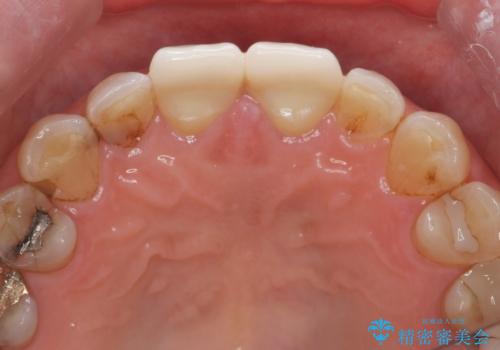

ディープバイト・噛み合わせが強いことからフルジルコニアクラウンを選択しました。

フルジルコニアクラウン治療について

フルジルコニアクラウンは全てジルコニアで生成されたセラミッククラウンで、前歯の噛み合わせが強い場合に切端の欠けを防ぎます。